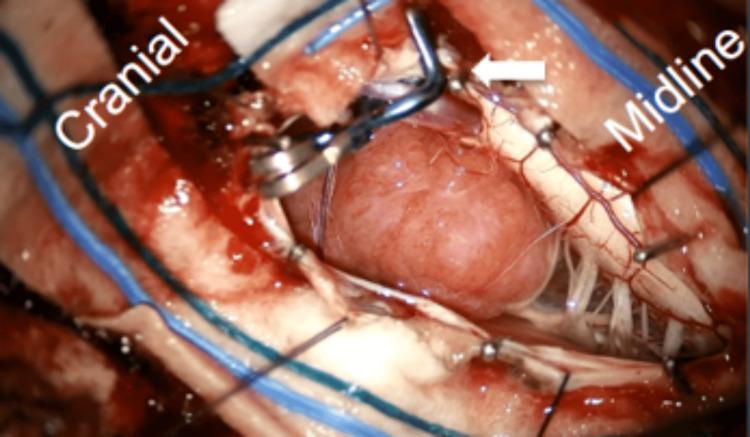

This report outlines the successful excision of an anterolateral foramen magnum meningioma (FMM) in a 69-year-old female patient who exhibited symptoms of vertigo, numbness in the left shoulder, and a fall. Neuroimaging revealed a lesion located at the anterolateral foramen magnum. The tumor was removed using a posterior midline suboccipital approach, with meticulous dissection performed around the left posterior inferior cerebellar artery (PICA). This artery was transposed with the aid of a Yasargil 5 mm curved temporary fenestrated clip (Aesculap AG & Co., Tuttlingen, Germany) to enable a Simpson grade 2 resection. The postoperative recovery was smooth, resulting in discharge on the third day, and histopathological analysis confirmed the diagnosis of an angiomatous meningioma, classified as CNS WHO grade 1. This case highlights the practicality and efficacy of PICA transposition during the resection of anterolateral FMM, showcasing the innovative application of a temporary fenestrated clip to stabilize the vessel while maintaining vascular integrity, thus allowing for safe tumor removal. This technique presents a promising approach for the management of complex foramen magnum lesions, yielding favorable results.

本报告概述了一名69岁女性患者成功切除前外侧枕骨大孔脑膜瘤(FMM)的病例。该患者出现眩晕、左肩麻木和跌倒症状。神经影像学检查显示病变位于前外侧枕骨大孔。采用枕下后正中入路切除肿瘤,在左小脑后下动脉(PICA)周围进行细致解剖。借助Yasargil 5mm弯曲临时开窗夹(德国图特林根的蛇牌股份公司)将该动脉移位,以实现辛普森2级切除。术后恢复顺利,患者于第三天出院,组织病理学分析确诊为血管母细胞型脑膜瘤,分类为世界卫生组织中枢神经系统1级。该病例突出了在切除前外侧FMM过程中PICA移位的实用性和有效性,展示了临时开窗夹在稳定血管同时保持血管完整性方面的创新应用,从而实现安全的肿瘤切除。该技术为复杂枕骨大孔病变的治疗提供了一种有前景的方法,取得了良好效果。